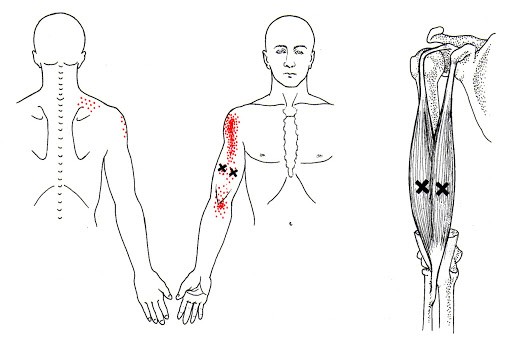

위 그림들에 붉게 표시된 부분이 해당 근육에 문제가 생겼을 때 통증을 일으키는 부위입니다. 교통사고 혹은 낙상과 같이 심각한 급성 사고가 아니라면 "뼈"에 통증을 호소하기에는 무리가 있고 아마도 근육의 과도한 사용으로 인해 트리거포인트가 방사통을 뿜어내는 것이 아닌가 생각됩니다.

이를 해결하기 위해서는 충분한 마사지가 필요한데요,

위와 같이 팔을 위치시키고 무릎(정확히는 정강이뼈)과 체중을 이용해 전완을 충분히 마사지해줍니다.